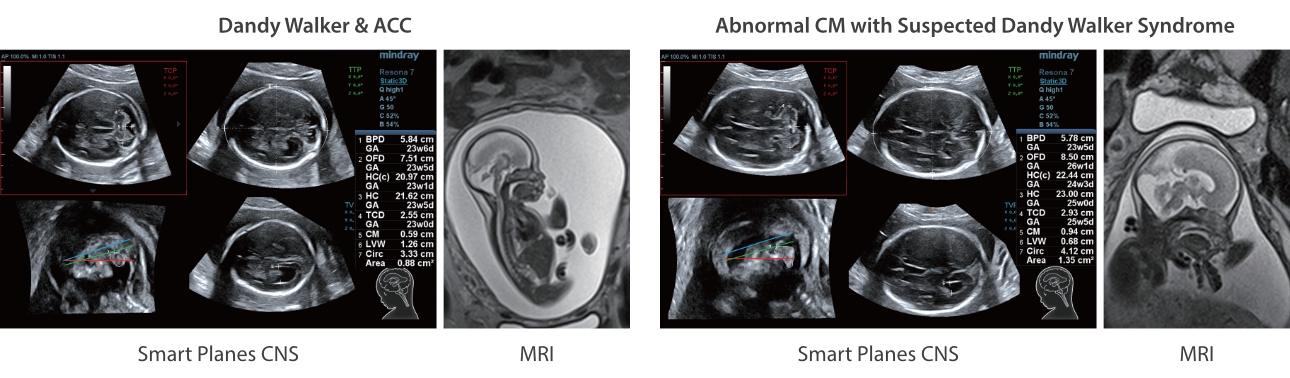

Assim como o n├Łvel de qualidade de imagem premium, o Resona 7 tamb├®m melhora as capacidades de investiga??o cl├Łnica com o revolucion├Īrio Fluxo V para avalia??o hemodin?mica vascular e a aquisi??o de plano mais inteligente do conjunto de dados 3D para diagn├│stico CNS fetal. Combinando a opera??o mais intuitiva baseada em gesto de multi-toques e todos os recursos cl├Łnicos essenciais, Resona 7 est├Ī realmente conduzindo novas ondas na inova??o de ultra-som.